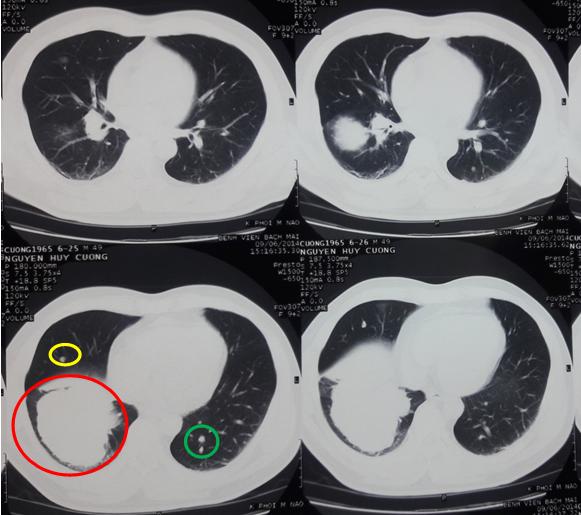

-       Chụp cắt lớp vi tính lồng ngực: U thùy dưới phổi phải kích thước 6 x 7cm, các nốt mờ rải rác 2 phổi.

Hình 1: Hình ảnh chụp cắt lớp vi tính lồng ngực trước điều trị (Vòng tròn đỏ: u thùy dưới phổi phải, kích thước 7 x 6cm, vòng tròn vàng: nốt vệ tinh phổi phải, vòng tròn xanh: nhân di căn phổi trái).